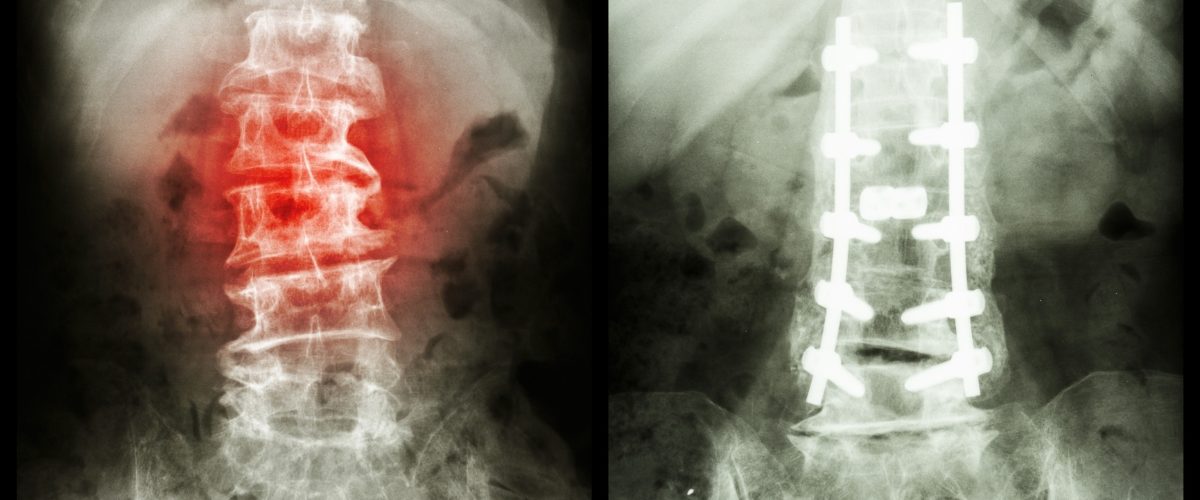

cirurgia de espondilolistese é uma intervenção indicada principalmente para casos em que o deslizamento da coluna leva à compressão dos nervos, à deformidade do tronco e à dor lombar que não pode ser controlada por meio de medidas clínicas. A intervenção consiste basicamente na estabilização das vértebras com parafusos, promovendo a fusão do segmento acometido pelo problema.

Os principais objetivos da cirurgia de espondilolistese são aliviar a dor associada à alteração, estabilizando a região da coluna onde a vértebra deslizou para fora do lugar e devolvendo capacidade funcional ao paciente. Em alguns casos, não há necessidade de trazer a vértebra de volta a seu lugar original, fazendo apenas redução parcial e a fixação para evitar que ela continue se movendo.

Existem diferentes técnicas que podem ser utilizadas na cirurgia de espondilolistese, sendo que a maioria delas se baseia na artrodese das vértebras, ou seja, na fusão das estruturas por meio da fixação com parafusos e dispositivos intersomáticos. A fixação é feita a partir da colocação de hastes e parafusos de titânio, acrescidas da colocação de dispositivos intersomáticos, sendo a preferência do Dr. Rodrigo Amaral, dispositivos anteriores (ALIF) ou laterais (LLIF/PTP), priorizando o uso de técnicas minimamente invasivas sempre que possível.